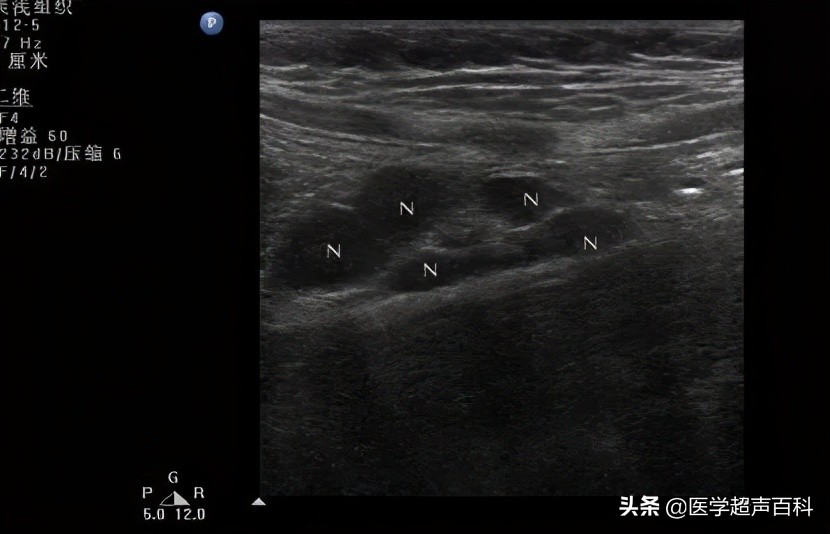

肠系膜淋巴结肿大超声表现:簇状增大的淋巴结,每簇≥3个,淋巴结的短径>5mm或长径>10mm;淋巴结内多无血流信号或呈星点状。

●肿大淋巴结多位于脐周或右下腹或两处均有。

●肿大淋巴结呈椭圆形,肾形结构回声存在,表面光滑,皮髓质分界清,中心髓质呈高回声,周围皮质为低回声。

●肿大淋巴结呈散在、串珠状、堆状分布,偶有重叠,无融合及钙化。

●大小多在2.0cm以下,2.0cm以上少见。

●部分患儿肠间隙及盆腔可见积液,最宽暗区<1.2cm。

●全部肿大淋巴结血流信号沿淋巴门分布,呈点条状血流信号,树枝状血流信号少见。